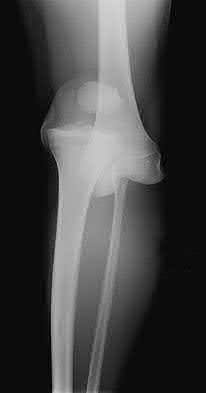

Figure A is an AP radiograph of a posterior knee dislocation. Figure B is a lateral showing the same injury.